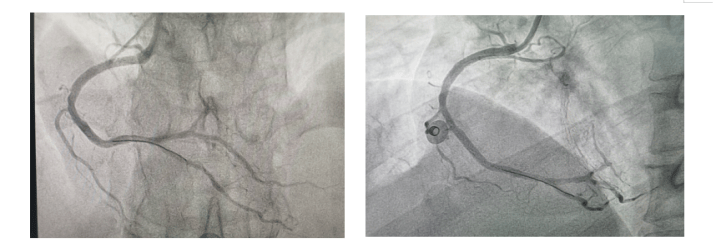

回旋支最重处植入支架一枚!患者顺利下台!

图片尺寸2000x2667

术前回旋支严重狭窄

图片尺寸367x328

左冠造影提示回旋支一分支通往瘤体,可见瘤体分为两叶